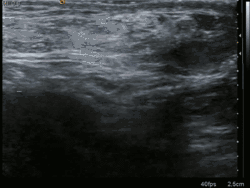

Ultrasound image of inguinal hernia. Moving intestines in the inguinal canal with respiration.

Medical imaging

A physician may diagnose an inguinal hernia, as well as the type, from medical history and physical examination.[20] For confirmation or in uncertain cases, medical ultrasonography is the first choice of imaging, because it can both detect the hernia and evaluate its changes with for example pressure, standing and Valsalva maneuver.[21]